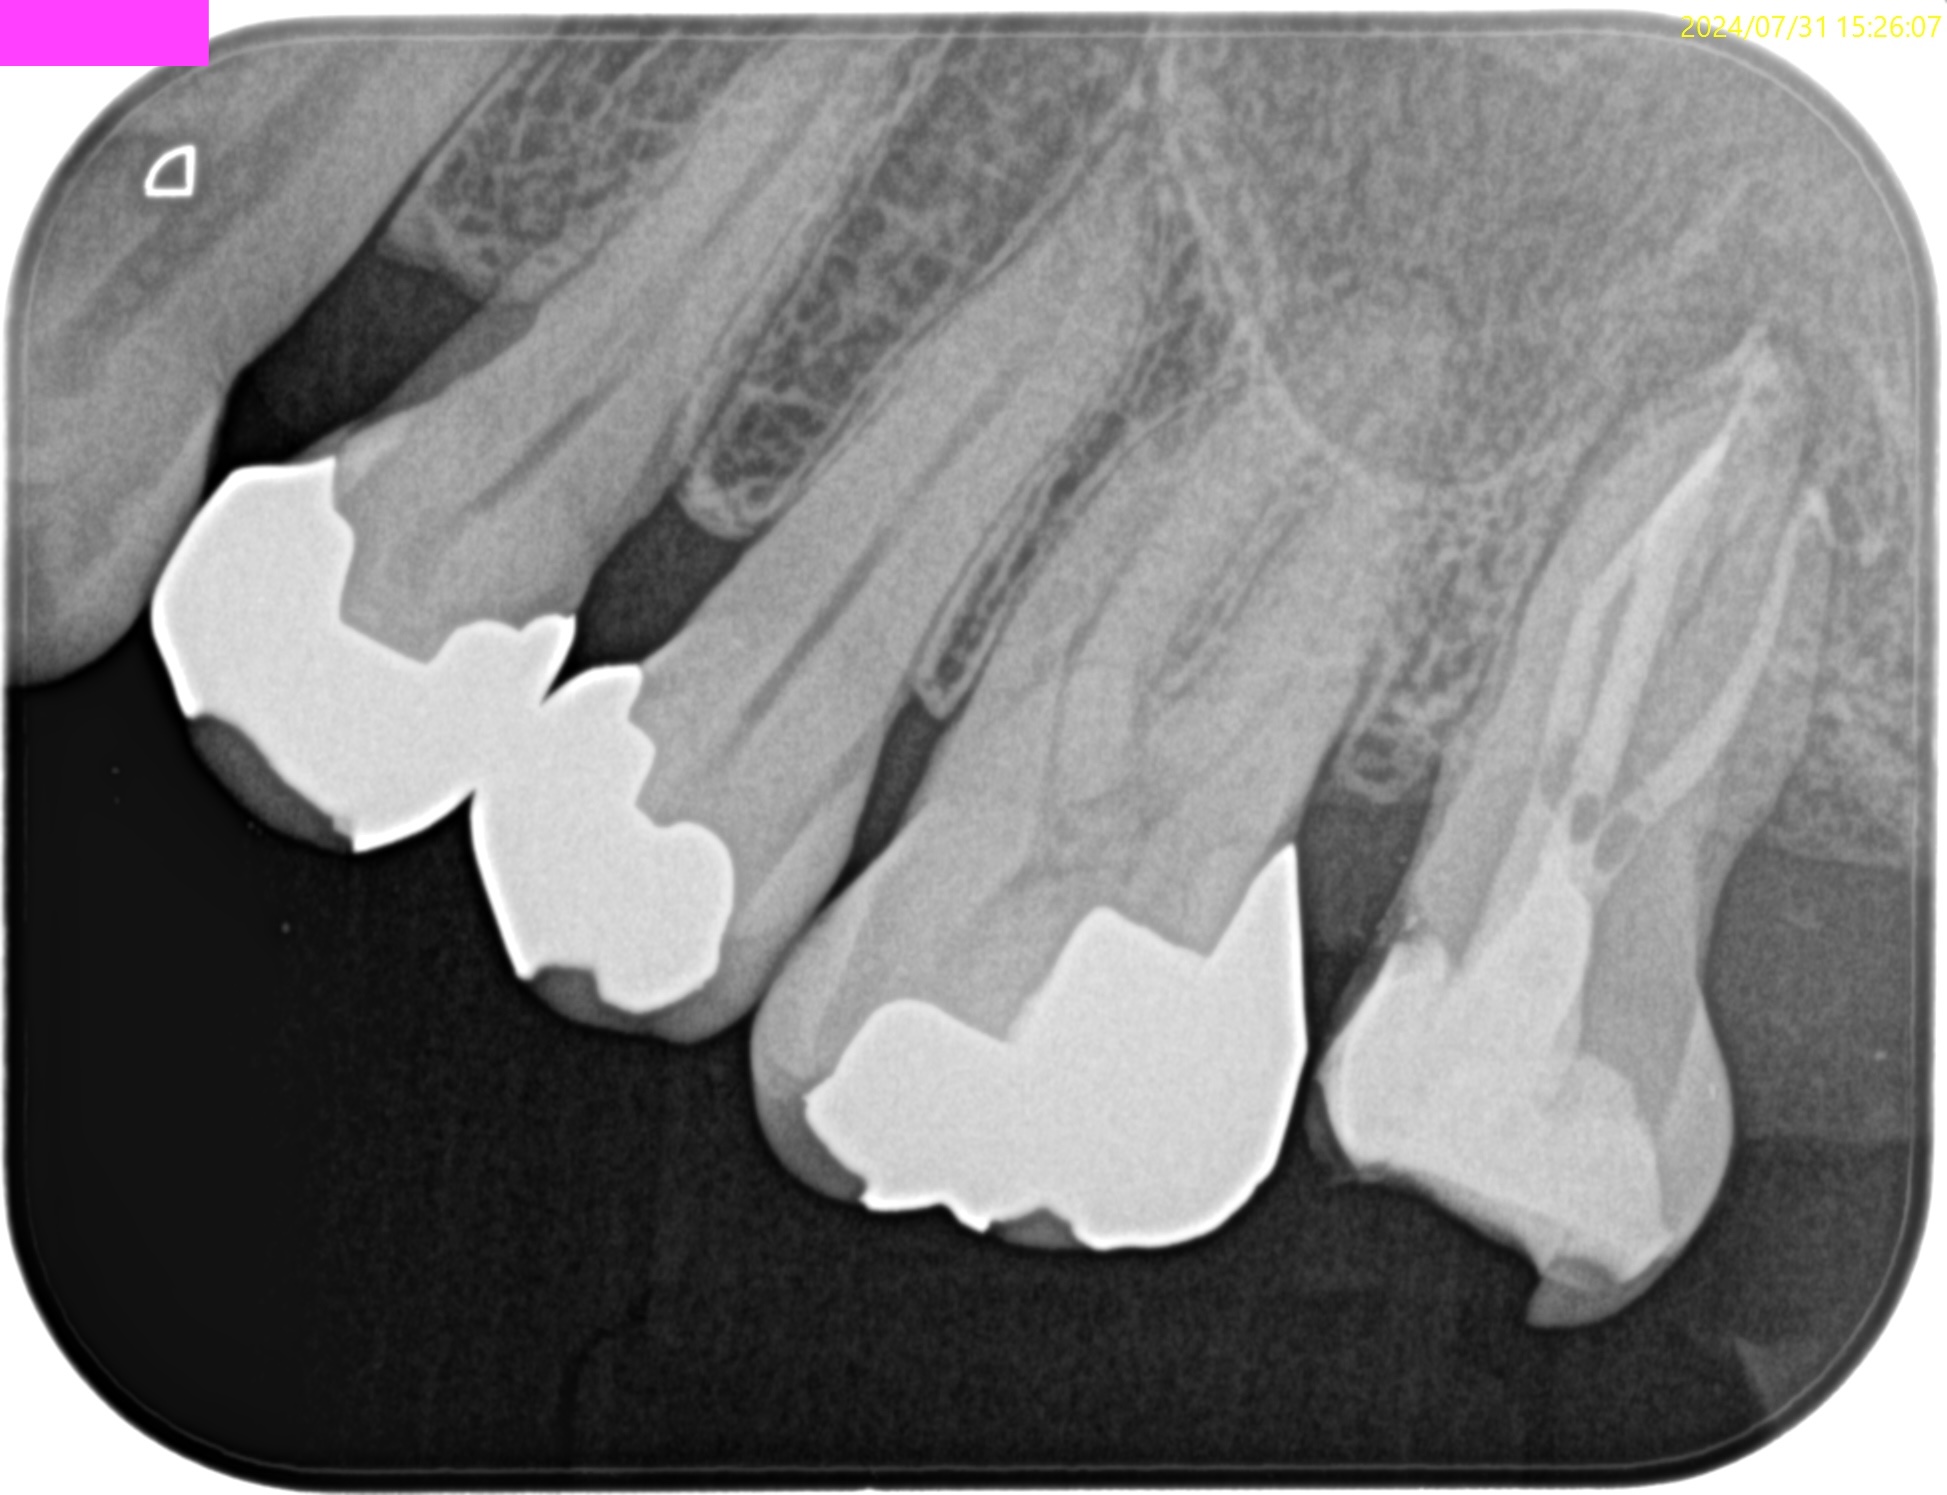

PA(2024.7.31)

#15 RCT(2024.7.31)

術後にPA, CBCTを撮影した。